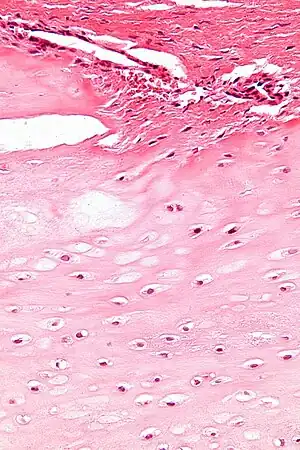

| Enchondromas are present in Maffucci syndrome | |

Maffucci syndrome is a very rare disorder in which multiple benign tumors of cartilage develop within the bones (such tumors are known as enchondromas).[1] The tumors most commonly appear in the bones of the hands, feet, and limbs, causing bone deformities and short limbs.[1]

The enchondromas affect the extremities and their distribution is asymmetrical. The most common sites of enchondromas are the metacarpal bones and phalanges of the hands. The feet are less commonly afflicted. Disfigurations of the extremities are a result. Pathological fractures can arise in affected metaphyses and diaphyses of the long bones and are common (26%). The risk for sarcomatous degeneration of enchondromas, hemangiomas, or lymphangiomas is 15-30% in the setting of Maffucci syndrome. Maffucci syndrome is associated with a higher risk of CNS, pancreatic, and ovarian malignancies. Multiple enchondromas may present in 3 disorders: Ollier disease, Maffucci syndrome, and metachondromatosis. It is important to make the distinction between these diseases, particularly Ollier disease and Maffucci syndrome. Ollier disease is more common than Maffucci syndrome, and presents with multiple enchondromas often in a unilateral distribution. However, hemangiomas and lymphangiomas are not seen in Ollier disease. Metachondromatosis demonstrates autosomal-dominant transmission and presents with both multiple osteochondromas and enchondromas.